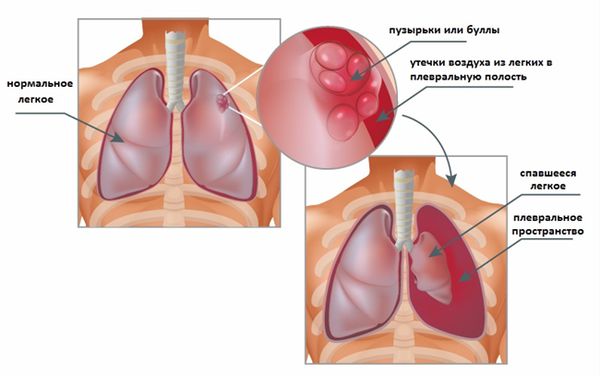

Схемы дыхания: Пневмоторакс на изображениях